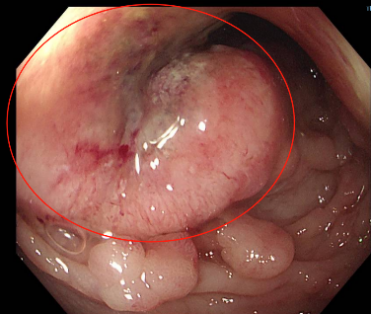

在肠镜检查时,医生看着屏幕,觉得“眼花缭乱”,密密麻麻的肠息肉有数百枚!

(肠息肉—癌前病变—肿瘤)